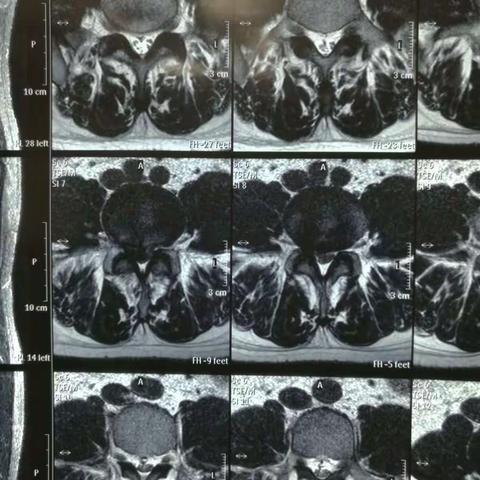

腰4/5椎间盘突出,后纵韧带钙化,椎间孔镜下髓核摘除,椎间孔扩大成形减压,神经根松解(进修学习资料)

2017-08-03 59阅读